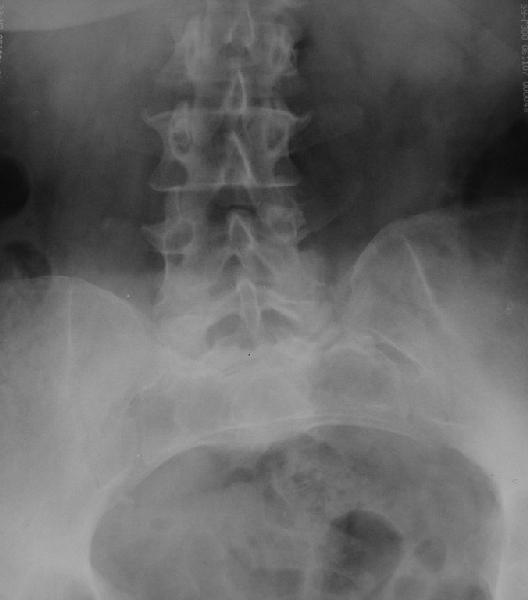

У больной 53 лет в последний год появились сильные боли в пояснице.

3 года назад при нефрэктомии по поводу гидронефроза была перфорация кишки, перитонит, сепсис, колостома. Месяца 2 в реанимации. Все это завершилось благополучно, колостома вскоре была закрыта.

При обследовании выявлен анкилоз тазобедренного сустава в приведении. Видимо, в период пребывания в тяжелом состоянии появились гетеротопические оссификаты. За исключением того, что осталась одна почка, сейчас других медицинских проблем нет.

Пациентку в первую очередь беспокоят боли в спине, на отсутствие движений в суставе она вроде и не жалуется. Вопрос насчет тактики. Корсет и анальгетики вряд ли решение. Первый вариант - удаление оссификатов и эндпротезирование, второй - корригирующая остеотомия в проксимальном отделе с устранением порочного положения.

Второй вариант много проще и менее травматичен. Можно ли без размыкания сустава рассчитывать на существенное уменьшение боли за счет устранения перекоса таза?